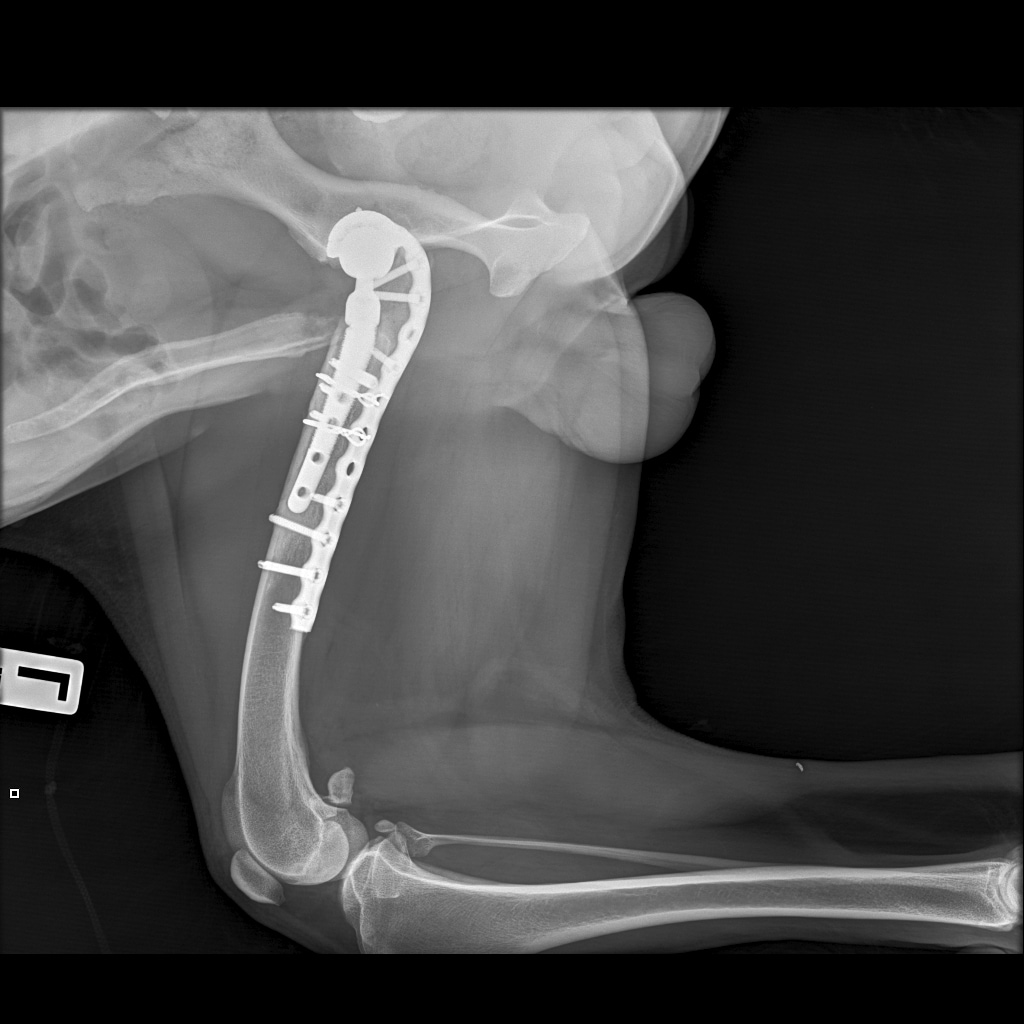

Выписка